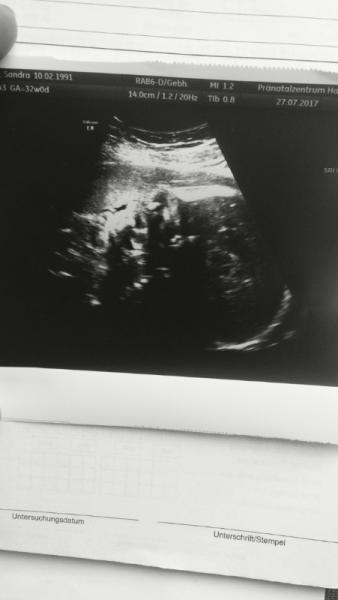

Guten Morgen Mädels Wir waren gestern nochmal im pränatalzentrum zur nachkontrolle und irgendwie ist jetzt wieder alles andere. also als allererstes hat sich unsere minimaus das erste mal überhaupt in der ss gezeigt &525; Der Rest ist etwas verwirrend. Für uns - aber ich hatte das Gefühl, auch für die Ärztin. Wo es letztes Mal eindeutig klar war, dass es der Darm war, meint sie, sind die darmschlingen jetzt besser. Es könnte wohl auch eine eierstockzyste sein. Man kann das nicht genau eingrenzen. Der Darm ist nicht mehr so krass etweritert aber da ist eben ne kreisrunde Zyste. Sie meinte wenn wir Glück haben, geht das nach der Geburt von allein Weg wenn es durch die Östrogene kommt. Aber sie kann uns das jetzt nicht versprechen. Sie meinte man wird schauen ob sie abführen kann und Ultraschall und so bei Emily machen... &300; Alles andere ist top. Sie hat auch 300 Gramm seit letzte Woche zugenommen. Jetzt bin ich wieder etwas verwirrt. Zwar ganz positiv. Aber meine eigene "eierstockzyste" damals war eierstockkkrebs &532;&531; wenn man so im Internet liest, dann sind solche eierstockzysten bei weiblichen feten echt sehr oft. Meist muss auch nicht operiert werden. Wir vertrauen nun einfach auf unsere Maus und warten ab was die Kinderärzte am Dienstag im Krankenhaus sagen, vllt können sie das ja auch nochmal anders beurteilen.